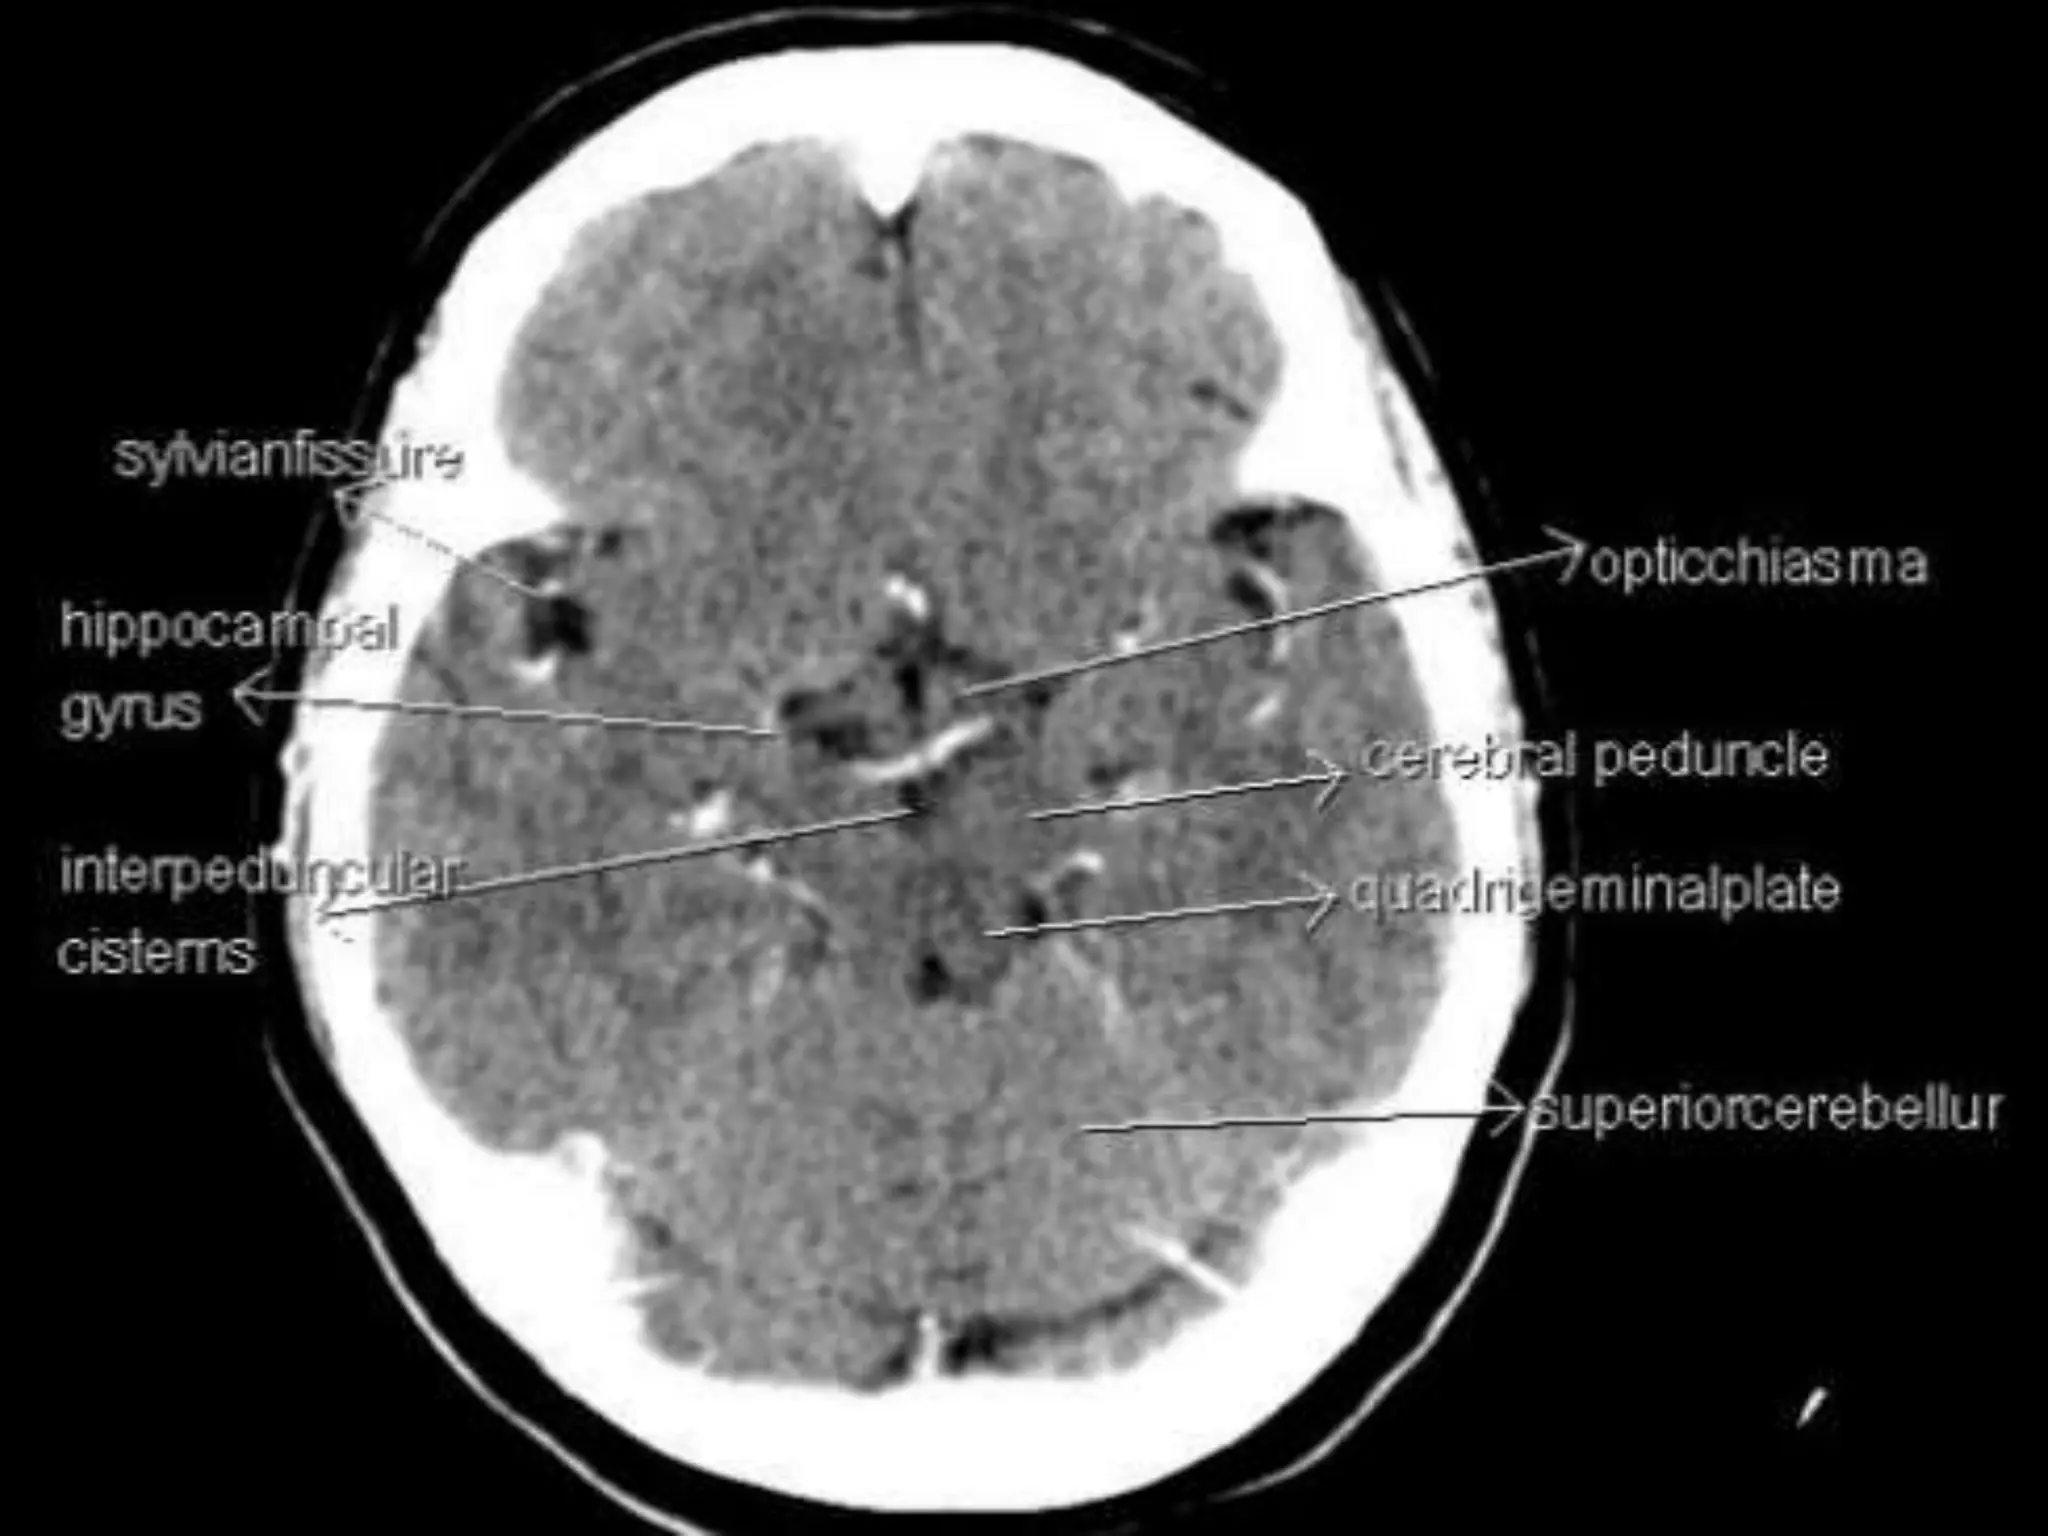

The two cerebral hemispheres are separated by

interhemispheric fissures and falx cerebri. On the lateral surface of the

brain, the sylvian fissure (lateral fissure) and the rolandic fissure (central

fissure) separate the cerebral hemisphere into the frontal lobe, temporal

lobe, parietal lobe, and a line drawn from the parieto-occipital sulcus

onto the preoccipital notch, delineating the boundaries of the parietal

and temporal lobes from that of the occipital lobe.

The two cerebralhemispheres are separated by interhemispheric fissures and falx cerebri. On the lateral surface of the brain, the sylvian fissure (lateral fissure) and the rolandic fissure (central fissure) separate the cerebral hemisphere into the frontal lobe, temporal lobe, parietal lobe, and a line drawn from the parieto-occipital sulcus onto the preoccipital notch, delineating the boundaries of the parietal and temporal lobes from that of the occipital lobe. The frontal lobe, the largest of all the brain, has four principal gyri: the precentral gyrus and the superior frontal, middle frontal, and inferior frontal gyri. The precentral gyrus, parallel to the central sulcus, together with the anterior bank of the central sulcus, comprises the primary motor area, which is one of the most important cortical areas for movement. Rostral to the precentral sulcus is the premotor area, another important area for movement. The middle frontal gyrus contains Brodmann’s area 8, known as the frontal eye field, which is important for conjugate eye movements. Another important motor area for speech called Broca’s area, is located at the triangular and the opercular parts of the inferior frontal gyrus in the dominant hemisphere.